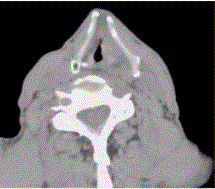

患者男,60岁,声音嘶哑半年,CT表现如下图。诊断正确的是A.声门区喉癌B.声门上喉癌C.喉正常表现D.喉结核E.喉乳头状瘤F.喉憩室

问题 患者男,60岁,声音嘶哑半年,CT表现如下图。 诊断正确的是

选项 A.声门区喉癌 B.声门上喉癌 C.喉正常表现 D.喉结核 E.喉乳头状瘤 F.喉憩室

答案 A

解析 A